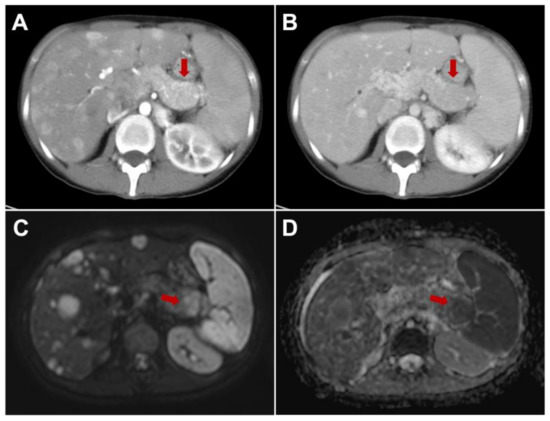

- Hayoz, R.; Vietti-Violi, N.; Duran, R.; Knebel, J.F.; Ledoux, J.B.; Dromain, C. The combination of hepatobiliary phase with Gd-EOB-DTPA and DWI is highly accurate for the detection and characterization of liver metastases from neuroendocrine tumor. Eur. Radiol. 2020, 30, 6593–6602. [Google Scholar] [CrossRef]